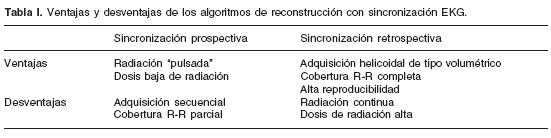

La tomografía computada (TC), inventada por Godfrey Hounsfield en 1972, ha tenido una evolución insospechada y un empleo prácticamente ilimitado.8 Mientras los sistemas de primera generación adquirían una sola imagen en aproximadamente 300 seg, en la actualidad los equipos de cuarta generación realizan la adquisición de hasta 256 imágenes en tan sólo 400 mseg, es decir 900–1,000 veces más rápidos que los aparatos de primera generación.8,9 La TC multidetector (TCMD) fue desarrollada coronaria y tomografía cardíaca. hacia finales de la década de los 90, y es considerada actualmente como el método no invasivo de elección para la evaluación vascular del tórax. Sin embargo, su papel en el estudio del corazón se encontraba limitado debido al movimiento cardíaco rápido y continuo, a la compleja anatomía cardiovascular y a las pequeñas dimensiones de las arterias coronarias (Tabla I).

Las imágenes se adquieren con acoplamiento electrocardiográfico (ECG), es decir, existe sincronización entre el latido cardíaco del paciente y la adquisición de las imágenes.16 Existen dos formas de adquisición: prospectiva y retrospectiva. 5,6,16,18 (Tabla I).